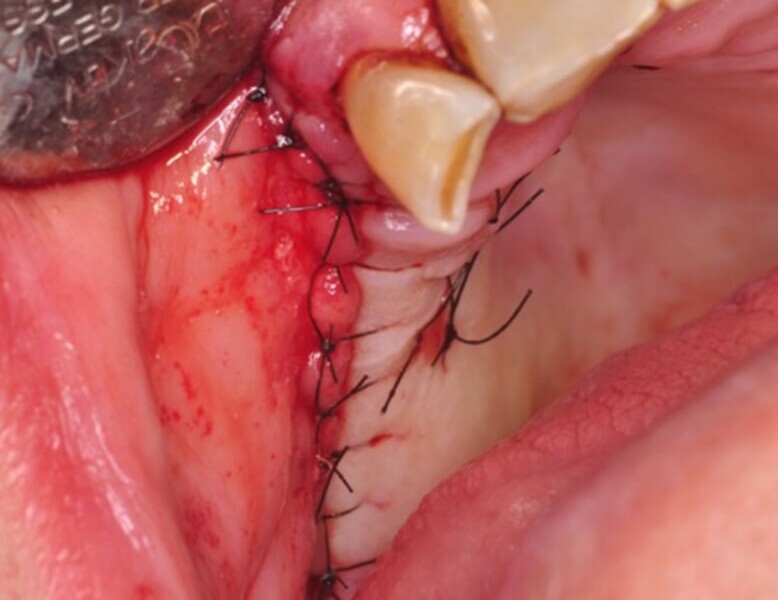

Osteonekroza występująca po zastosowaniu bisfosfonianów